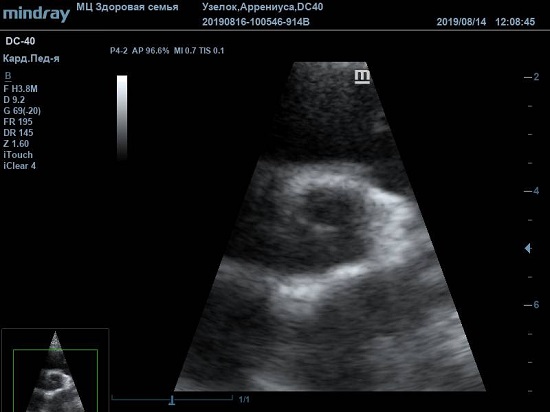

Существует вариантная анатомия, например, наросты Ламбла или гипертрофия узелков Аррениуса на полулуниях аортального клапана. Узелки и наросты увеличивают занимаемый объем полулуния, при этом нарушая конгруэнтность поверхности створок или полулуний клапана. В итоге закрытие осуществляется не полностью, и возникает легкая недостаточность. Именно такие случаи часто обнаруживаются у детей и не требуют специального лечения или пристального наблюдения.

Найти их очень просто, достаточно сечений LAXLV (длинная ось) и SAXBASE (короткая ось). Специфические крупные шаровидные структуры – узелки Аррениуса - на кончиках полулуний клапана обнаружил ультразвуковой прибор Mindray DC-40. В цветовом допплере без труда определяется аортальная регургитация легкой степени. Оценить её можно в CFM по соотношению JW/LVOT.